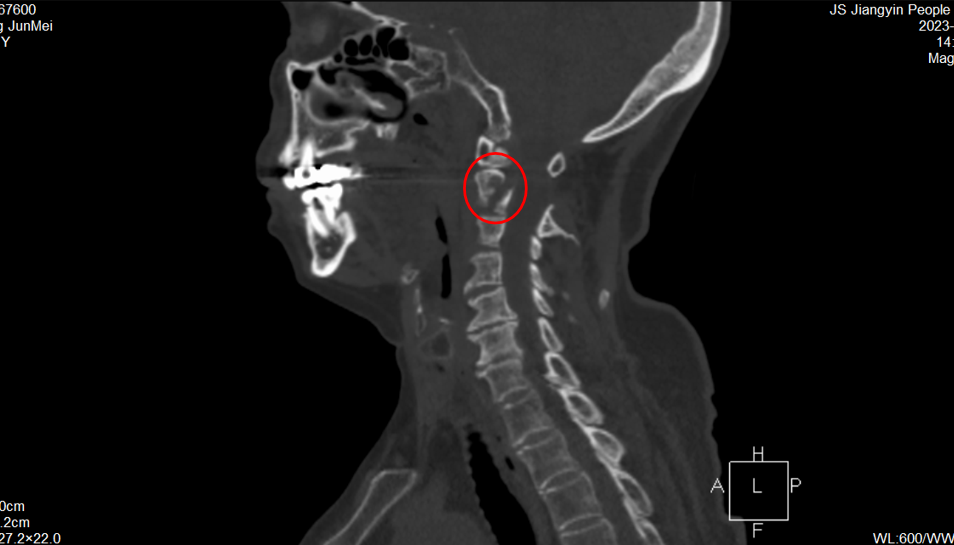

今年81歲的張奶奶因頸部外傷導致頸部疼痛伴活動受限入院就診。核磁共振檢查顯示,老人樞椎椎弓根骨折伴局部骨髓挫傷水腫,如若不及時手術,很快就會癱瘓、繼而影響呼吸功能,甚至危及生命。

張奶奶術前CT

老人手術指征明確,但樞椎區域骨折手術本就風險較大,加之患者高齡且長期臥床,易出現肺部感染、骨質流失更多不愈合等嚴重并發癥,對醫護人員的手術技術和圍手術期管理能力要求極高。